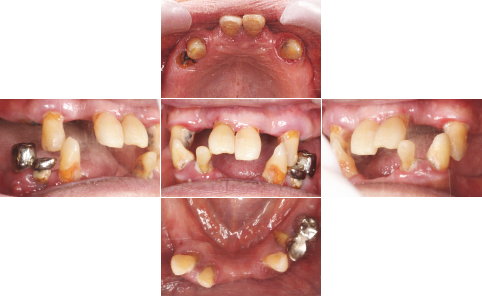

| 治療前 | 治療後 |

| 上顎はいつ抜けてもおかしくない状態であったため、直ちにAll-on-4を施術しました。 下顎も重度の歯周病で状態は良くありませんでしたが、患者様の希望もあり、抜歯せず、現在経過観察中です。 |